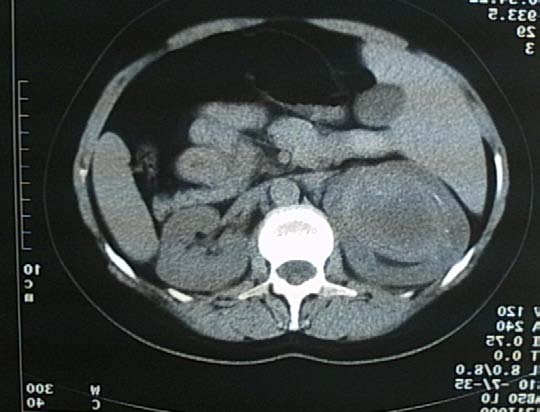

The enhanced CT images revealed a right kidney cystic mass, with a 10 cm diameter, thick irregular walls with contrast enhancement, hyperdens content, and no pathological lymph nodes or distant metastases. The diagnosis was a Bosniak IV.

The characteristic findings were thick and irregular wall and heterogeneous contents of the cystic mass. The cyst contained bloody fluid and a hemorrhagic degenerating mass. Pathohistological examination showed evidence of malignant hemorrhagic renal cyst. Which is treated by surgical intervention and usually nephroctomy.